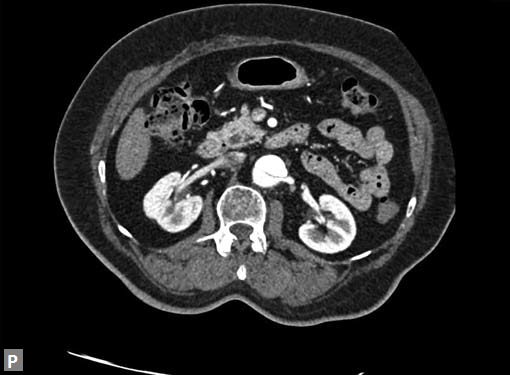

Any part of aorta can get affected by aneurysms. Focal

dilations can be saccular or fusiform. Atherosclerosis is

the most common cause. Tubercular and other infective

aneurysms, traumatic ones are also uncommonly seen. Size

of the aneurysm, proximity to origin of main vessels, relation

with branching and bifurcation, presence of mural thrombus

are the critical information sought on CT.

Contained leak, rupture are the feared complications.

Aortoenteric fistula is a rare but potentially catastrophic

complication. Aneurysmal dilation is common in ascending

aorta (Figs 19W to Y).

CT is also useful in surveillance of diagnosed aneurysms.